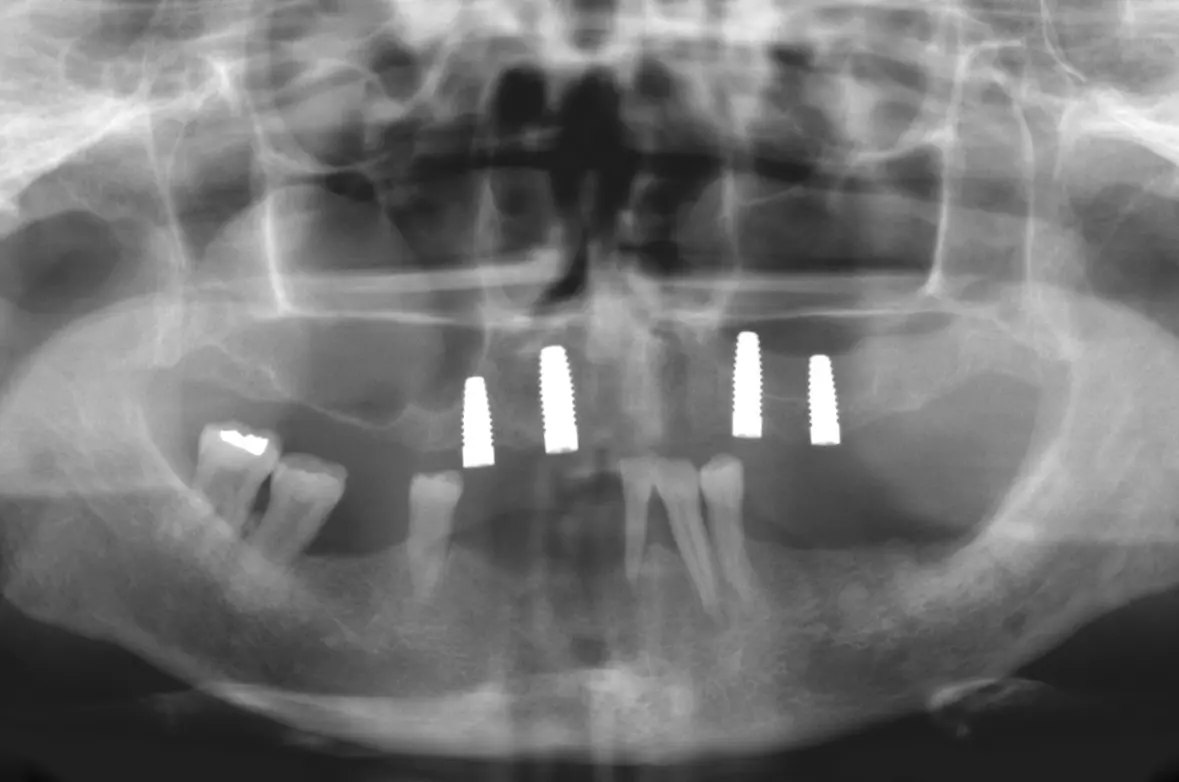

Die Knochensituation im Oberkiefer war ausreichend für 4 Implantate zwischen 13 und 23 (2 x Zeramex XT 4,2/10 mm und 2 x 4,2/12 mm). Die Freiendsituation im Unterkiefer wurde mit 2 Implantaten im 3. Quadranten gelöst (2 x Zeramex XT 4,2/10 mm). Für den restlichen Unterkiefer war eine festsitzende Brücke von 34, 33, 32, 44, 46 auf 47 geplant. Da neu und seit diesem Zeitpunkt verfügbar, kamen verschraubte Docklocs® Zirkon Abutments aus Zirkonkeramik zum Einsatz.

Abb. 1: OPG vor Behandlungsbeginn. Dr. Michael Leistner

Abb. 1: OPG vor Behandlungsbeginn.